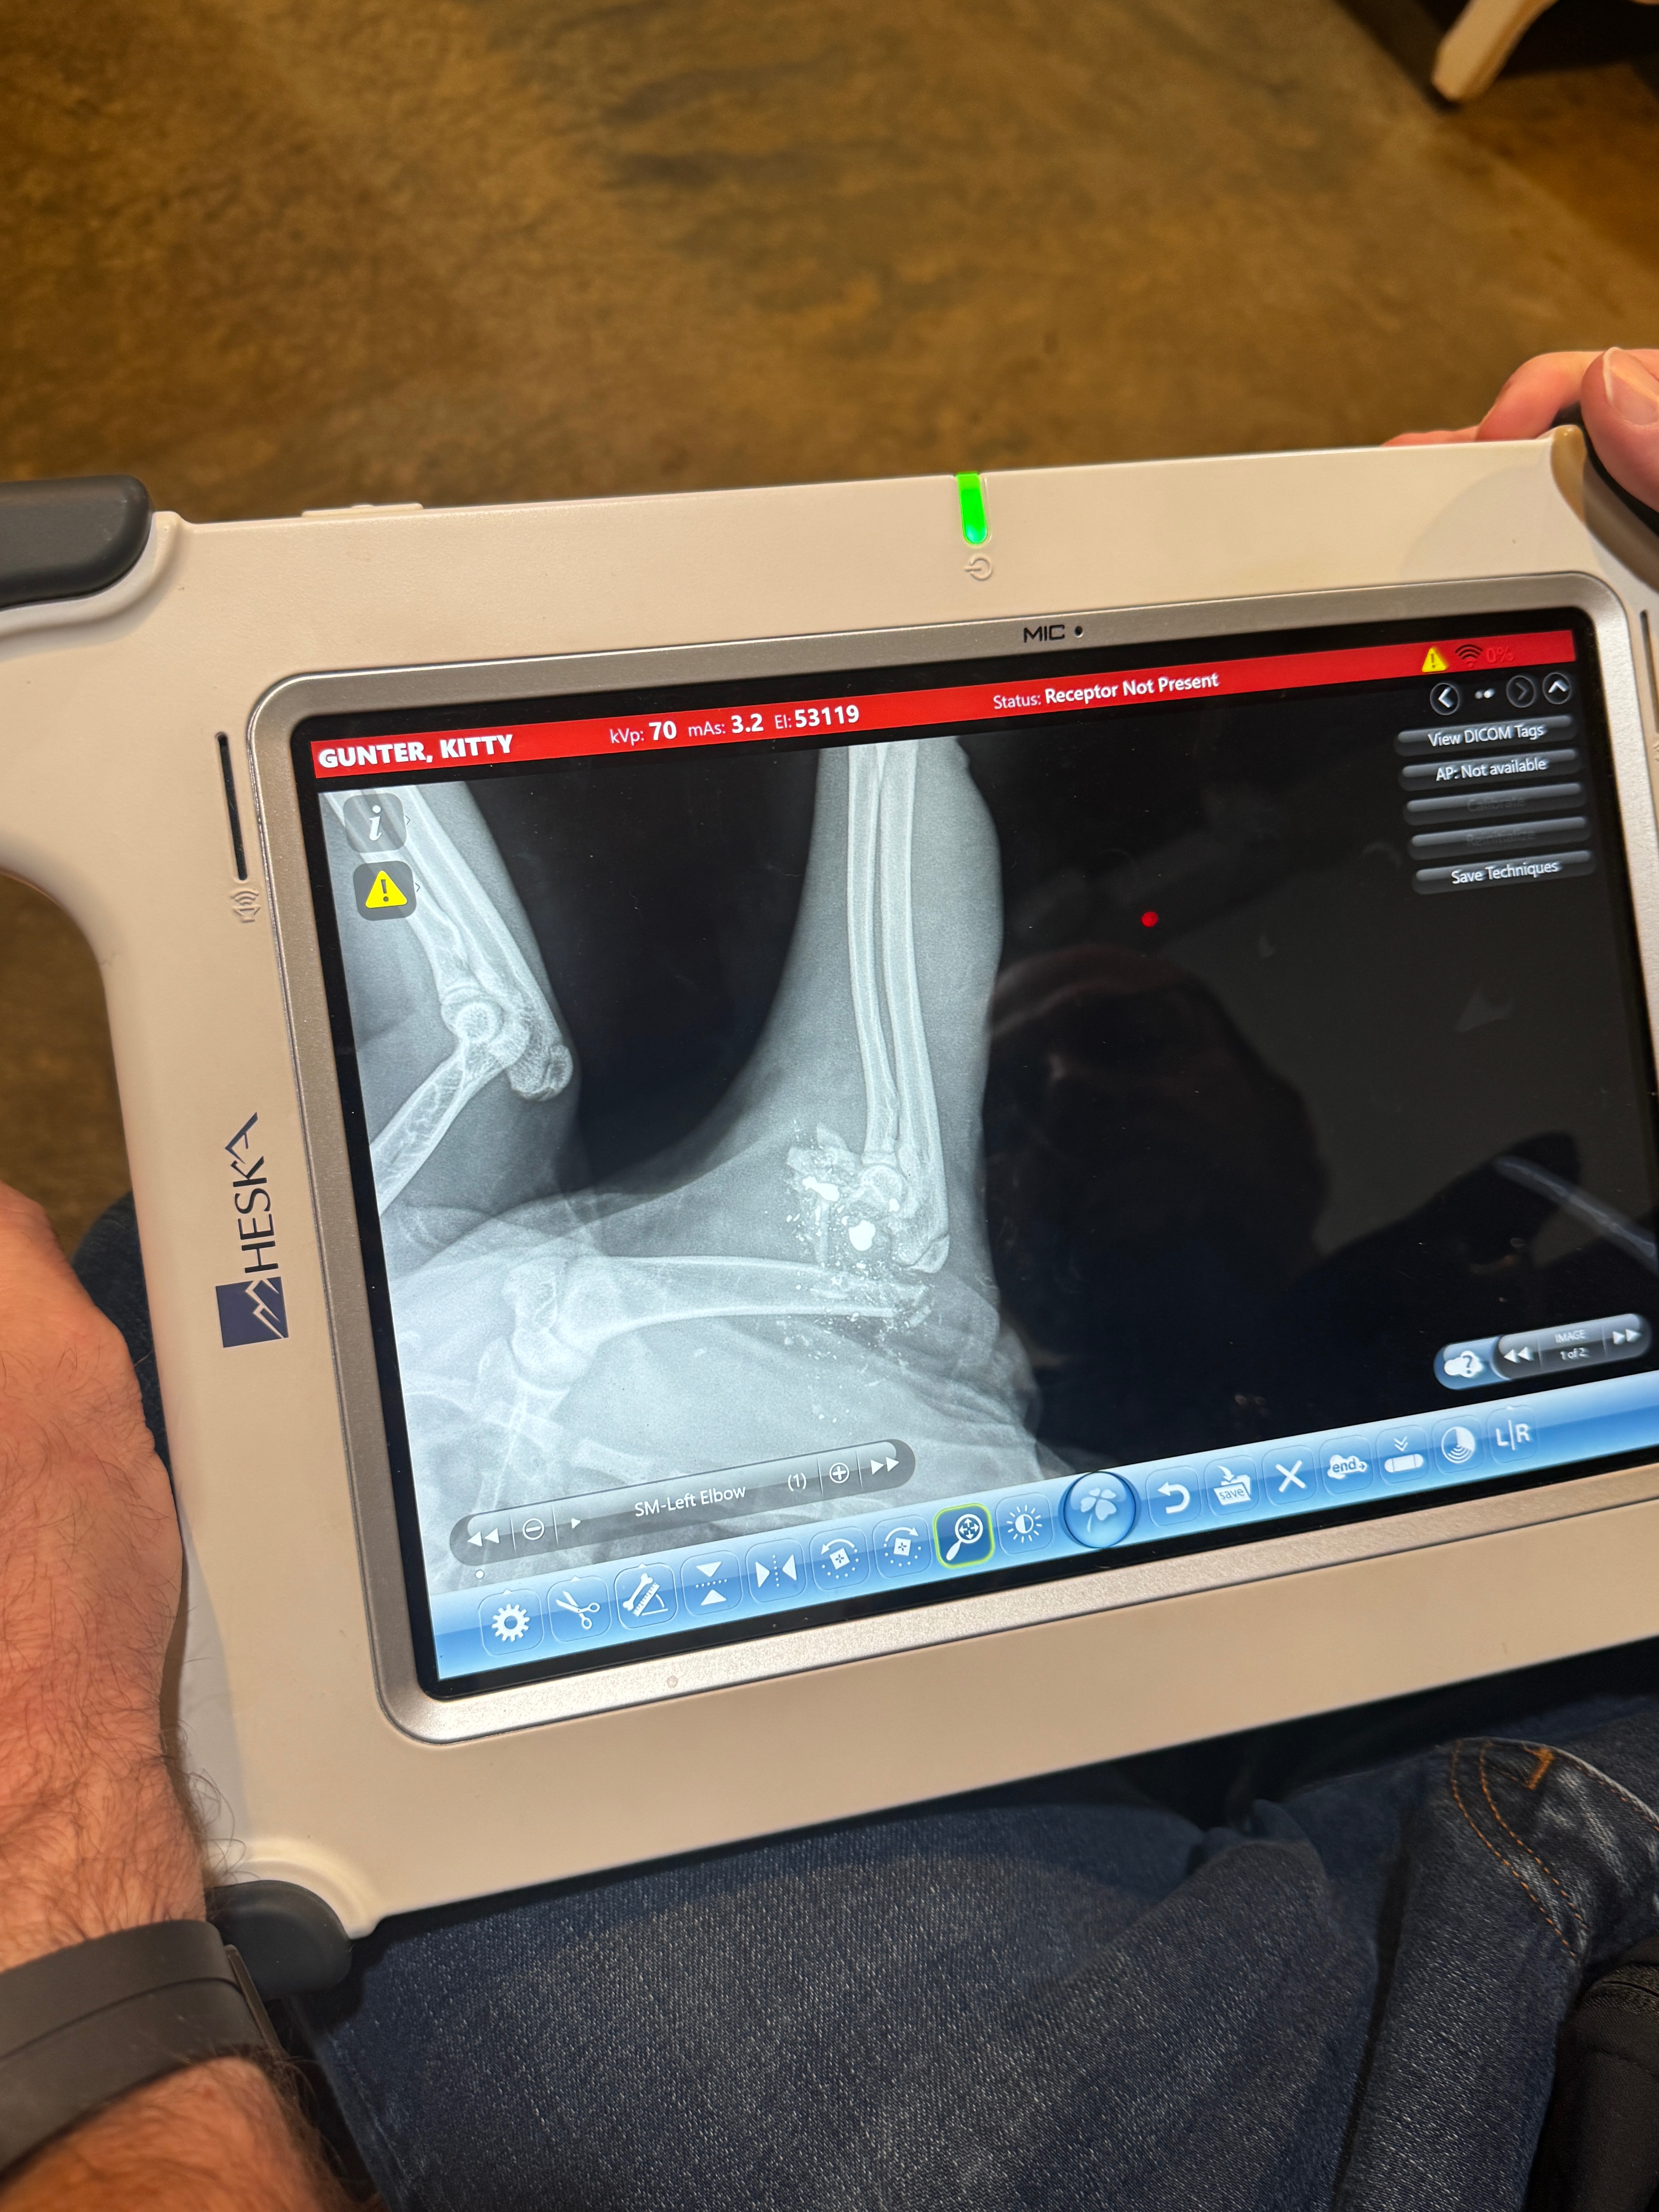

Recently, AC was shot by a neighbor, and the bullet shattered his leg past the point of fixing. The only way to save him is an urgent amputation surgery. If we can't raise the funds soon, the final option may be to put him down, which is something I desperately want to avoid. AC is currently on antibiotics, but the vet said the surgery needs to happen as soon as possible to prevent infection and give him the best chance at recovery.